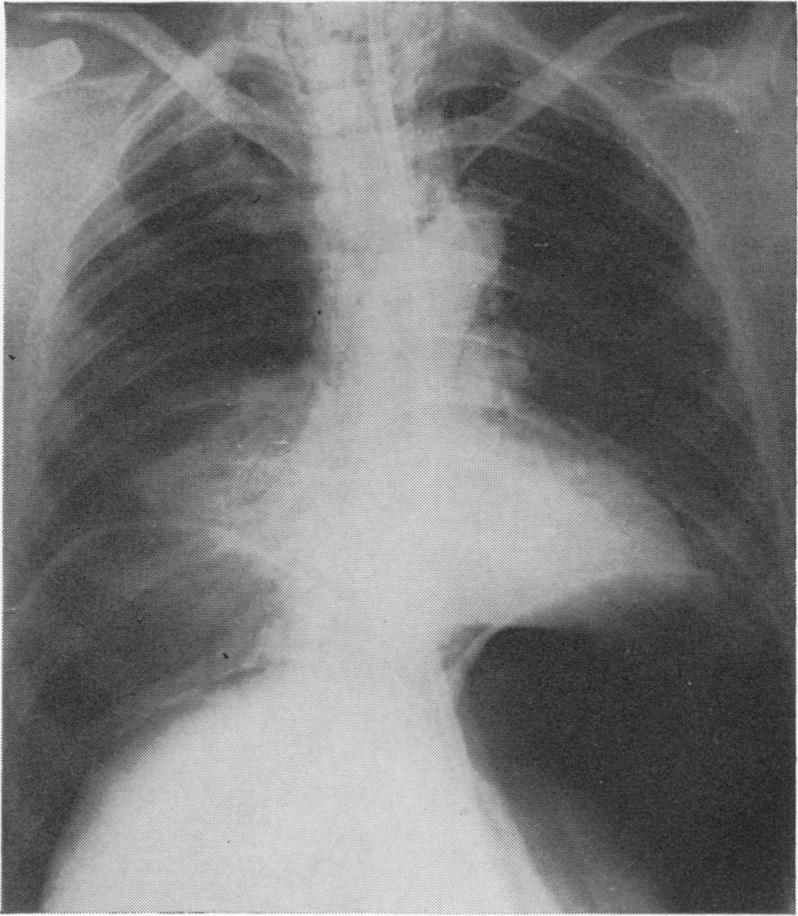

FOSTER J H, JOLLY P C, SAWYERS J L, DANIEL R A

Ann Surg. 1965 May;161(5):701-9. doi: 10.1097/00000658-196505000-00008.